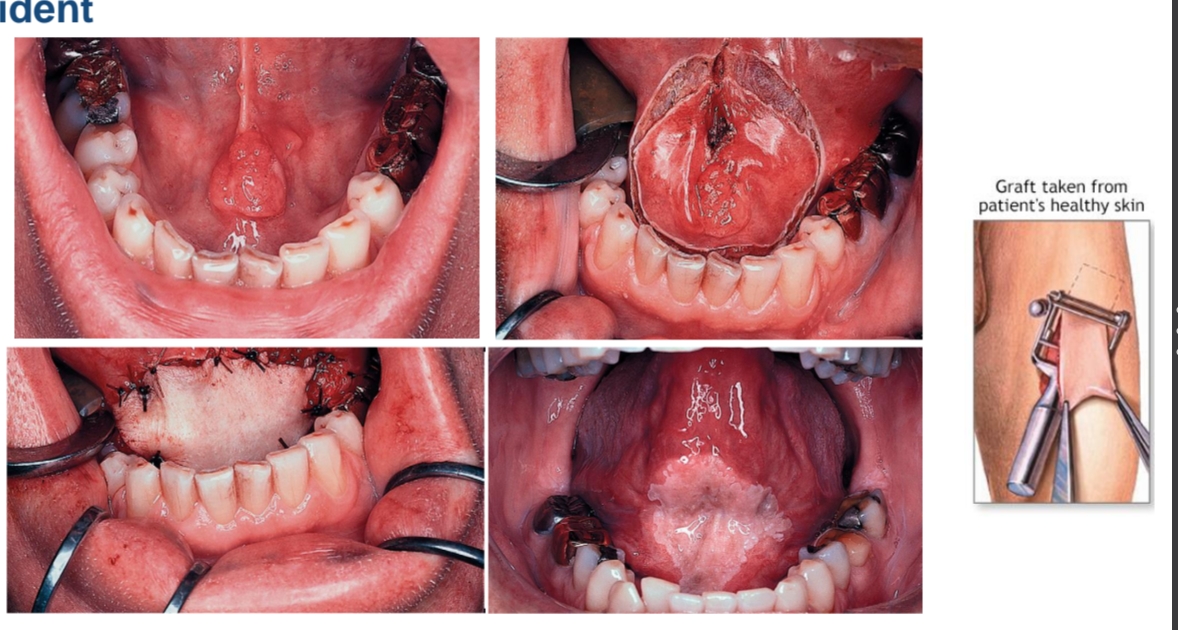

Reconstructie: weefseltransfer

Huident

Weefsels uit de buurt, met voedende bloedvaten (gesteelde flap) → met bloedvat

Weefsels op afstand, met voedende bloedvaten (vrije flap)

Tong, mondbodem, gingiva onderkaak

Zeer kleine tongtumoren:

Resectie (partiële glossectomie)

en ‘primair sluiten’

Of huident

Esthetisch

Functioneel: tongtip!l

wondcontractie → de flap gaat krimpen door litteken vorming

Vrije flap

sensibikiteit aangepast!

Radial forearm flap

Microvasculaire anastomose → conecteren bloedvaten

Donorsite morbiditeit → plek op arm kan ook sensibiliteit hebben!

Gesteelde flap (FAMM flap wang) vs voorarmflap